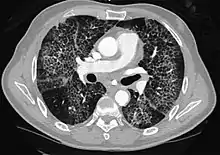

Crazy paving refers to a pattern seen on computed tomography of the chest, involving lobular septal thickening with variable alveolar filling. The finding is seen in pulmonary alveolar proteinosis,[1] and other diseases.[2] Its name comes from its resemblance to irregular paving stones, called crazy pavings.[3]

There are variety of causes for crazy paving patterns: infection, cancer, blood related disorders, diseases caused by inhalation of particles, and idiopathic disease. Specific lung disorders that can cause such patterns are: pneumocystis pneumonia, mucinous bronchioloalveolar carcinoma, pulmonary alveolar proteinosis, sarcoidosis, nonspecific interstitial pneumonia, organizing pneumonia, exogenous lipoid pneumonia, adult respiratory distress syndrome, and pulmonary hemorrhage syndromes.[4]